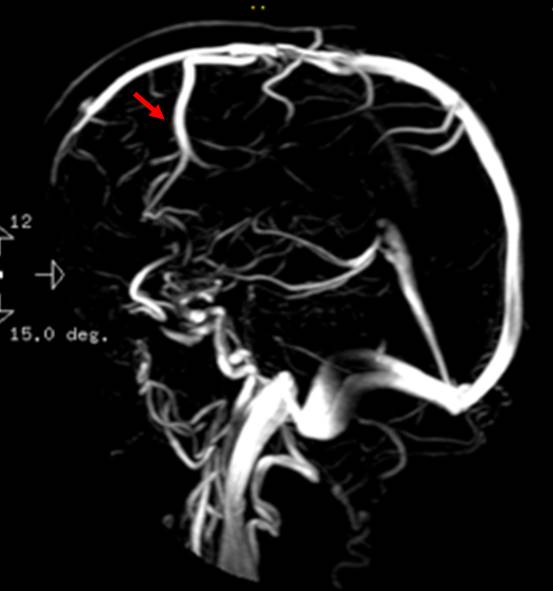

Angiográficamente, la imagen es característica, con una fase arterial normal o con discreta captación en fase capilar tardía, haciéndose realmente evidente en la fase venosa (►Figura 4).1,5